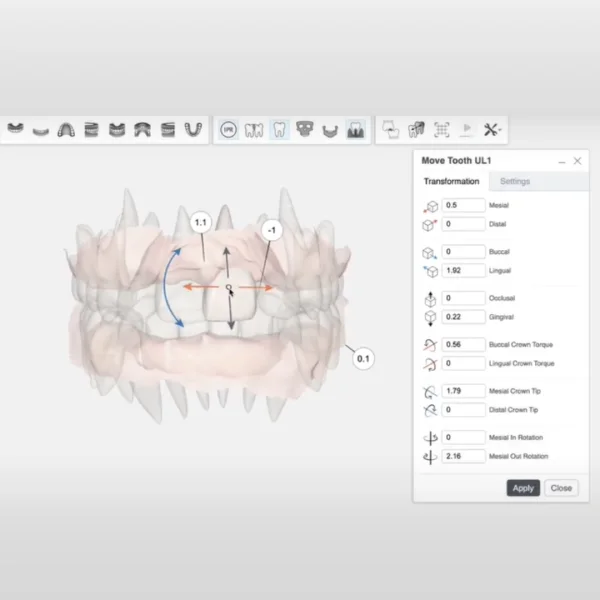

ทันตแพทย์จะใช้ซอฟต์แวร์ที่ขับเคลื่อนด้วย AI วิเคราะห์และวางแผนการเคลื่อนที่ของฟันแต่ละซี่อย่างละเอียด เพื่อคำนวณทิศทาง, การใช้แรง, และเวลาที่เหมาะสมให้ฟันเคลื่อนไปยังตำแหน่งที่ต้องการ

แขนกล (NiTi Arms) แต่ละชิ้นจะส่งแรงที่คำนวณไว้ล่วงหน้าไปยังฟันแต่ละซี่อย่างต่อเนื่องและเป็นอิสระต่อกัน ทำให้ฟันสามารถเคลื่อนที่ได้พร้อมกันโดยไม่ส่งผลกระทบต่อซี่อื่น

วางแผนการรักษา ด้วย AI Technology และ 3D Computer Imaging